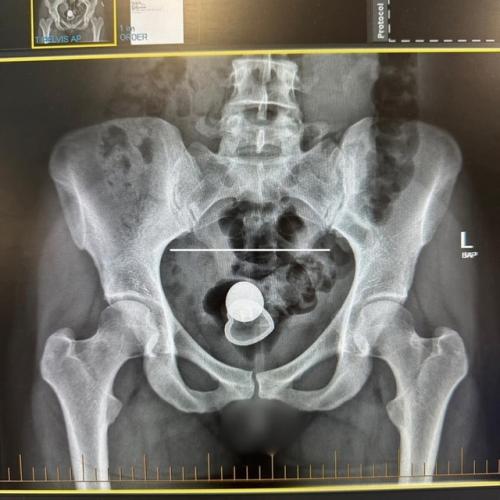

Она провела два дня в больнице из-за инородного тела в прямой кишке. Несмотря на отсутствие боли, актрисе трудно было справиться с позывами к дефекации, что и вынудило её обратиться за помощью. Врачи успешно операцию провели